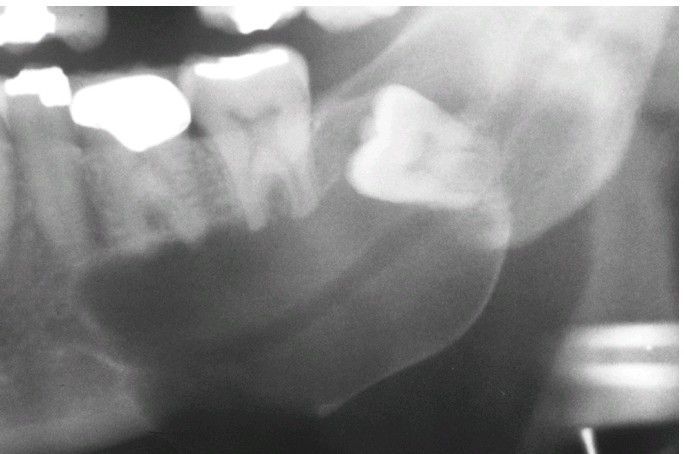

Dentigerous Cyst.

Lateral variety showing a large cyst along the mesial root of the unerupted molar. This cyst exhibited mucous cell prosoplasia.